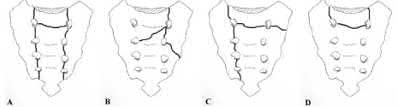

Question 4:

A 28-year-old sustains a laceration to the volar aspect of the digit in Zone II, requiring surgical exploration and flexor tendon repair. To prevent tendon bowstringing and maximize biomechanical excursion efficiency, which two annular pulleys are the most critical to preserve or reconstruct?